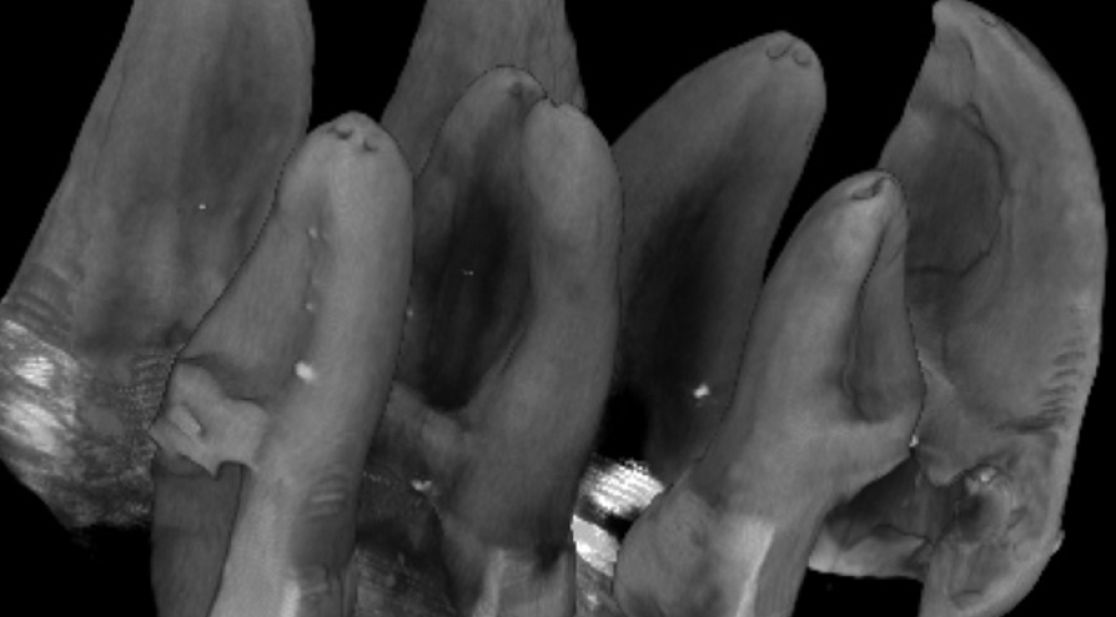

Department of Conservative Dentistry